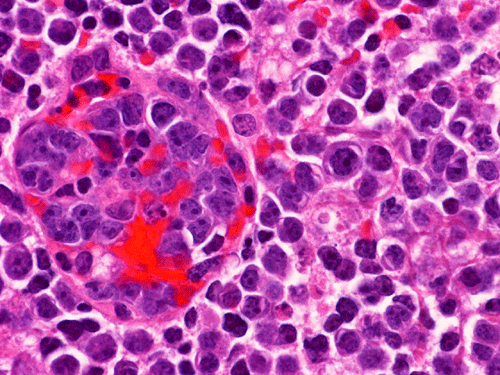

The material for permanent sections is largely semi-liquid in consistency. There are only very few fragments of cerebellar tissue that are infiltrated by the tumor. The bulk of the diagnostic material are solid sheets of neoplastic cells (Panel G). The cytologic features are similar to what we have observed in the cytologic preparation  (Panel H). In essence, the tumor is composed of solid sheets of large polygonal and rather monotonous atypical cells with a thin rim of cytoplasm and molding which lead to a mosaic pattern. These features are consistent with lymphoma. On immunohistochemistry, practically all the neoplastic cells are positive for leukocyte common antigen (LCA) (Panel I), CD20 (Panel J) and many of them are positive for CD79a (Panel K). Only reactive T-cells but not the large, atypical cells are positive for CD3 (Panel L). The neoplastic cells are essentially negative for Bcl-6 (Panel M) but some of them are positive for Bcl-2 (Panel N). The large atypical cells are negative for kappa and lambda light chains on immunohistochemistry. There is no immunoreactivity in the neoplastic cells for cytokeratin (AE1/AE3), S100, pan-melanoma marker (Mart-1, tryptase, and HMB-45).

DIAGNOSIS: Diffuse large B-cell lymphoma.

Similar to the systemic counterparts, diffuse large-B cell lymphomas of the CNS are characterized by large, pleomorphic lympyoid cells. Histologically, however, PCNSL shows the unique angiocentric infiltrating pattern, which is more prominent at the edge of the lesion. The tumor cells dissect and expand the perivascular network in a concentric manner which is best demonstrated by reticulin stain

[click here to see a picture]. Systemic DLBCL does not show this particular pattern of growth. The tumor infiltrates the brain parenchyma between blood vessels as small clusters and individual cells. Confluent areas of tumor may show necrosis, with residual viable tumor cells being found mostly around blood vessels. The boundary of the tumor may be relatively discrete, but it is more common for perivascular cuffs and single infiltrating lymphoma cells to be found at some distance from the tumor mass, extending far away from radiographically evident tumor margins. The malignant lymphocytes lack a cohesive appearance, do not form glands or other structures. The nuclei vary from round to indented or cleaved, and prominent nucleoli can be noted. The cells have only a small amount of basophilic cytoplasm. Variable numbers of mitotic figures and apoptotic cells are seen.

Immunophenotyping shows positive staining for CD20, CD19 and CD79a in large atypical cells and CD3 positivity in small, benign T-lymphocytes. Additional staining for immunoglobulin light chains (κ and λ) to demonstrate monoclonality and proliferation marker as MIB-1 (Ki-67) are useful in diagnostic workup. However, in poorly differentiated tumor, there may be a total lack of light chain on immunohistochemistry. MIB-1 is rarely used due to lack of correlation with prognosis. Flow cytometry can be helpful in establishing the phenotypic profile particularly when the tumor does not look like a clear cut diffuse large-B cell lymphoma. Immunohistochemistry for cytokeratin and markers for malignany melanoma are helpful in differential diagnosis.